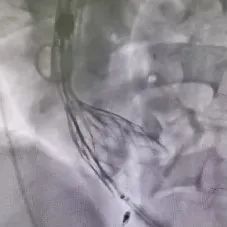

冠脉造影

冠脉硬化

LAD病变